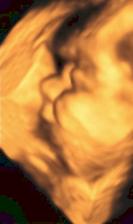

14.10.08 poradna - odebrána krev+moč-výsledky za 14dní, mimísek má 4cm a dostali jsme TĚHOTENSKOU PRŮKAZKU🙂)).............................................27.10.08 poradna - mimísek má 6,5cm, genetický test v naprostém pořádku, riziko se snížilo na 1/9050 - takže téměř žádné-huráááááááá!............................................. 19.11.2008 odběry krve na triplle testy v 16tt - negativní🙂))............................................. 16.12.2008 poradna - vše v pořádku.............................................18.12.2008 velký ultrazvuk - mimísek je v naprostým pořádku, srdčko i všechno ostatní funguje jek má🙂)))............................................. 13.1.2009 poradna + test na cukr............................................. 27.1.2009 poradna - cokrovka je negativní, můžeme mlsat dál🙂............................................. 13.2.2009 4D ultrazvuk-mimísek se nám pořád skovával za ručičky, ale nakonec jsme ho přemluvili a aspoň na chvilku se nám ukázal🙂)............................................. 17.2.2009 poradna- prcek už je hlavičkou dolů a připravenej jít ven, navíc mi strašně tvrdne břicho takže mi dr. zvýšil dávku magnézia a musíme ležet............................................. 2.3.2009 velký ultrazvuk v 31tt - prcek je v pořádku a už má 1700g ............................................. 17.3.2009 poradna - vše ok, prcek má 2100g ............................................. 18.3.2009 sepsání porodopisu ............................................. 26.3.2009 nástup na mateřskou🙂